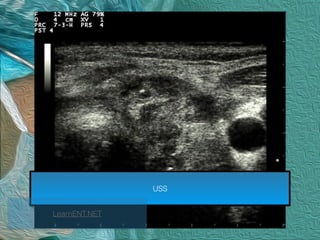

USS

LearnENT.NET

1. Hypoechogenicity

2. Irregular/microlobulated margins

3. Microcalicifications

4. Taller - than - wide

Kim, E.K et al. (2002) New sonographic criteria for recommending fine-needle aspiration biopsy of non-palpable

solid nodules of the thyroid. American Journal of Roentgenology, 178, 687–691.